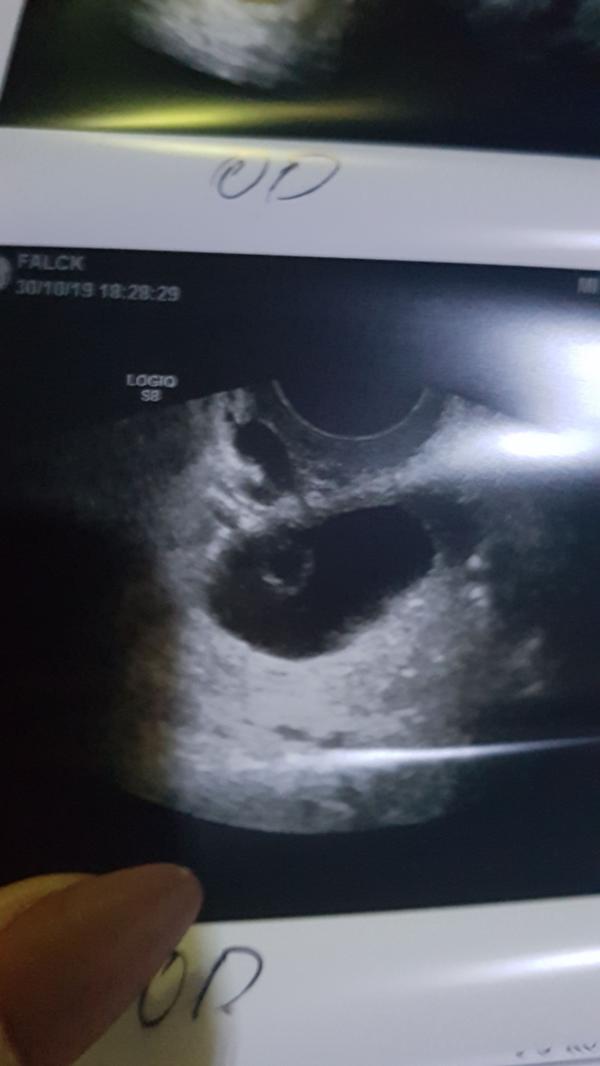

Девочки, у кого была киста желтого тела? Подскажите каких размеров и на какой день цикла? И посмотрите на фото пожалуйста, она у вас выглядела так? Ну или похожа хотя бы? Мне просто не могут определить что это за образование, уже 2 врачей прошла, 3 узистов и все плечами пожимают, говоря что это какая то жидкость в жидкости и только один узист предположил что это может быть киста желтого тела. Я уже себе места не нахожу, успокаивпет одно, что все говорят что это доброкачественное образование, но якобы очень необычное 🙈 #первыйпост

@kopilova.e.s88 тогда мои предположения, я думаю, верны. Фото качество так себе, но я бы сказала, что это фолликулярная киста яичника, это значит, что ваш фолликул рос рос и не лопнул вовремя и перерос в кисту. Поэтому и не было овуляции и тесты на нее отрицательны. А то включение внутри кисты- это тоже фолликул, как бы на заднем фоне, он тоже рос, но не дорос и сейчас идёт его регресс. @nikavytuleva похоже, да) но автор не беременна)

Мне одной кажется что это плодное яйцо и желточные мешок в нем ? 🙄

У меня беременность один в один фото 🤷🏻♀️

Скажите, какой у вас день цикла сейчас, вон то образлвание, внутри черного образования, похоже на фолликул, скорее всего это он и есть, как бы за кистой, т.к позади ткань яичника